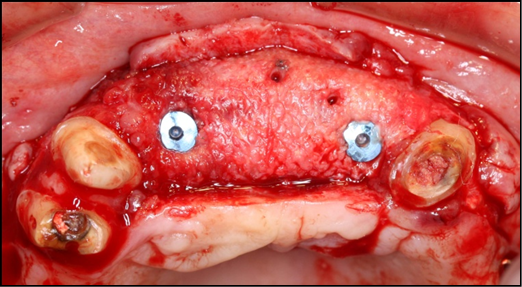

At the 8-months follow-up, a CBCT scan showed consolidation of the grafted material with the recipient bone (Figure 6). A second surgical procedure was conducted under local anesthesia and oral sedation in order to remove the titanium mesh. At this appointment, the pre-maxilla showed to be significantly augmented (Figure 7) with the dimension of 14 mm in height and 10 mm in width. The bone characteristics were soft, erythematous, with a cancellous texture. Four dental implants (Biomet 3I certain®, USA) were inserted, with no more than 25 Ncm2 of primary stability (Figure 8). The implants were uncovered 6 months later for initiation of the prosthetic rehabilitation using 4 single-unit crowns. One-year follow-up showed to be uneventful (Figure 9).

Figure 7.Re-entry at 8-monthspost-op shows a clinically significantly augmented maxilla. Occlusal viewshows implants (Biomet 3I certain®, USA) # 7 and 10 placed.